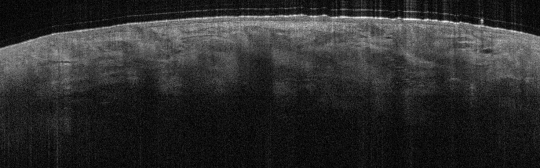

VA38: Upper Forehead, Left of Midline, Actinic Keratosis, Hypertrophic

- Arrows indicate base of epidermal thickening

VA36: Upper Forehead, Left of Midline, Adjacent, Normal